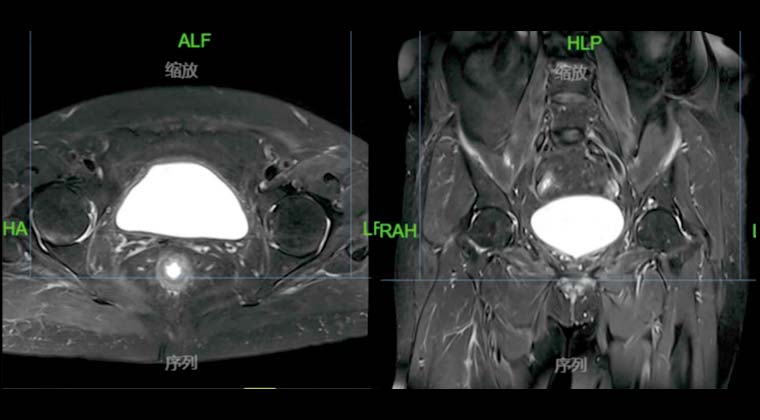

Рак мочевого пузыря

29.02021 проведено PET/CT обследование: выявлены множественные очаги на передней, задней стенках и дне мочевого пузыря, предполагается рецидив опухоли.

Проведена одновременная химиолучевая терапия (монотерапия цисплатином 20 мг/м² еженедельно) с облучением таза по VMAT 45 Гр, с локальным бустом мочевого пузыря 20 Гр, с применением IGRT.

Через месяц после лучевой терапии контрольное МРТ таза не выявило остаточных опухолевых очагов или признаков рецидива в мочевом пузыре.

До лечения:

После лечения: